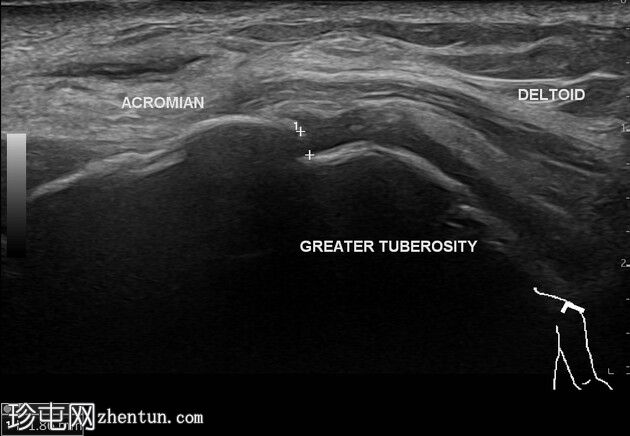

多平面

临床和X线片可见的肿块是一个起源于左侧肩锁关节并位于其上的不规则壁囊肿。囊肿内可见数个等回声至低回声区域,并伴有微小的强回声灶。囊肿周围及间隔可见血流信号。下方的肩锁关节可见关节囊增厚和骨质不规则。

超声显示肩峰肱骨间距缩小,肱二头肌长头在肱二头肌沟内消失,肱二头肌长头肌腱交界处下垂并伴有脂肪浸润,肩胛下肌颅侧纤维全层撕裂,尾侧纤维完整,冈上肌腱和冈下肌腱消失,小圆肌腱变薄且呈低回声,肱骨头软骨变薄,冈上肌-冈下肌脂肪浸润伴体积缩小,小圆肌回声正常但体积增大。